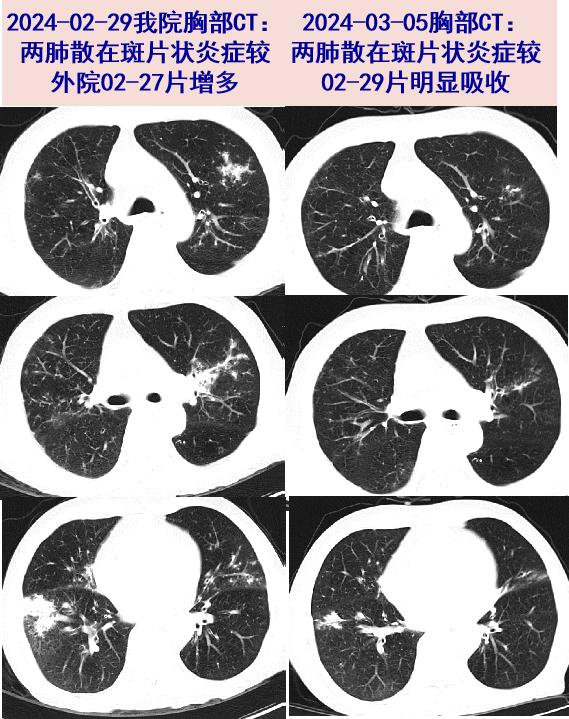

闻袜子得真菌性肺炎?——谈谈居住环境与肺病! [病例帖]